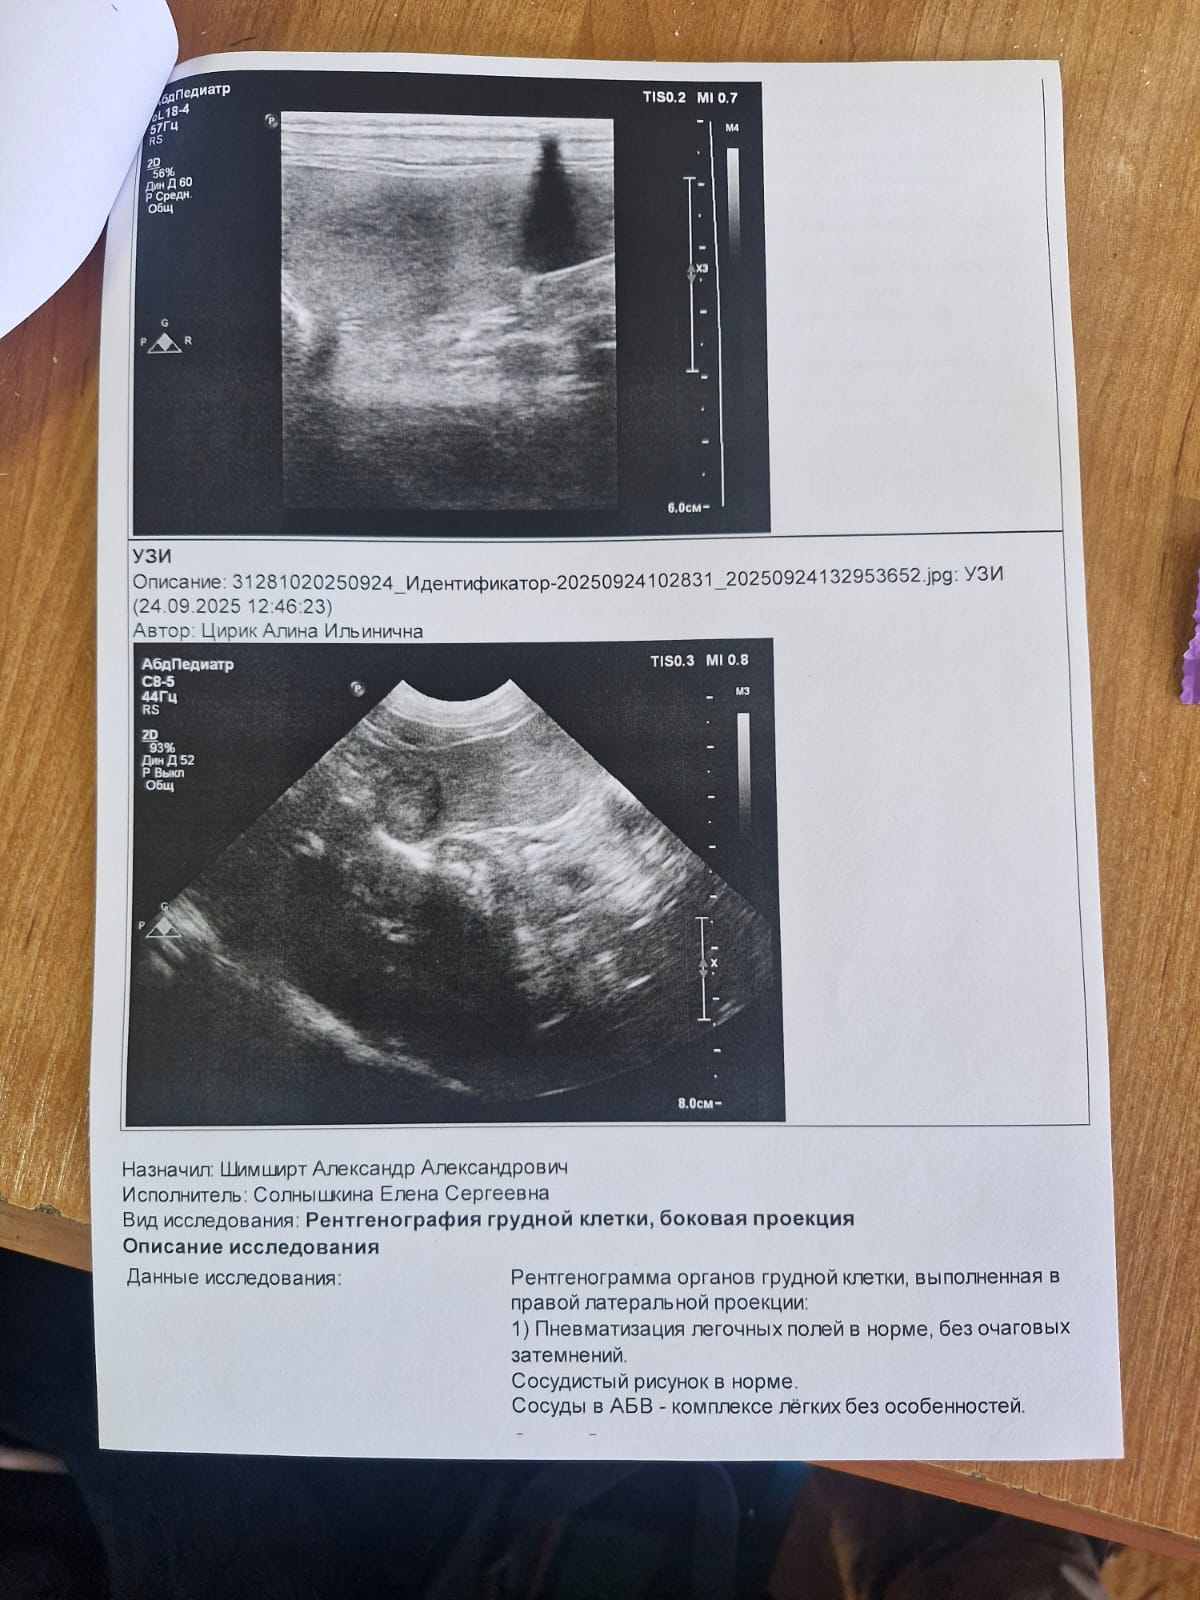

Колобушу сегодня возили в клинику. Новости не радостные. В лёгких на рентгене всё чисто. Но на УЗИ обнаружили два новых новообразования в селезёнке, пока они небольшие, нужно наблюдать. По мнению Шимширта, это скорее всего появились метастазы. Самое плохое, что так быстро появились. Сказал, следует наблюдать. Контрольный приём через месяц.